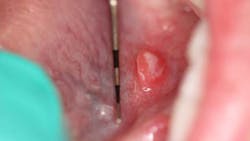

While performing the head, neck, and oral cancer screening exam, a raised, round soft-tissue lesion approximately 6 mm x 6 mm was observed under the left side of the tongue along the sublingual salivary gland ducts. The outside border was red and contained a white center. The lesion and area in general were not tender to palpation, and both mom and patient were unaware of its presence.

Definitive diagnosis: Aphthous ulcer (minor)

Apthus ulcers (minor) are “small superficial ulcers of the oral gland-bearing mucosa that occur episodically in clusters of one to five lesions.”1 It is the most common type of aphthous ulcer found.2 The lesions occur throughout the mouth, including the soft palate, floor of mouth, tongue, mucobuccal fold, buccal mucosa, lips, and movable mucosa (nonkeratinized).2